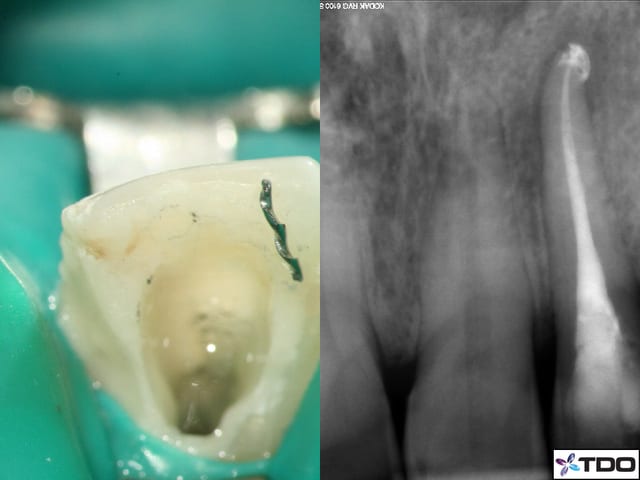

je te rassure, voilà la miènne...perfo réalisée sous loupes :-))))

le point rouge c'est moi :-), la lime C+ c'est là où est le canal :-)

mais je précise que c'était une RTC...de merde :-)